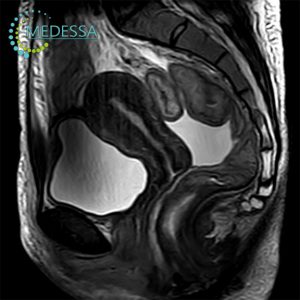

Pelvic MRI

For women:

- Lower abdominal or pelvic pain.

- Menstrual irregularities.

- Suspected endometriosis, fibroids, ovarian cysts.

- Infertility.

- Preoperative gynecological assessment.